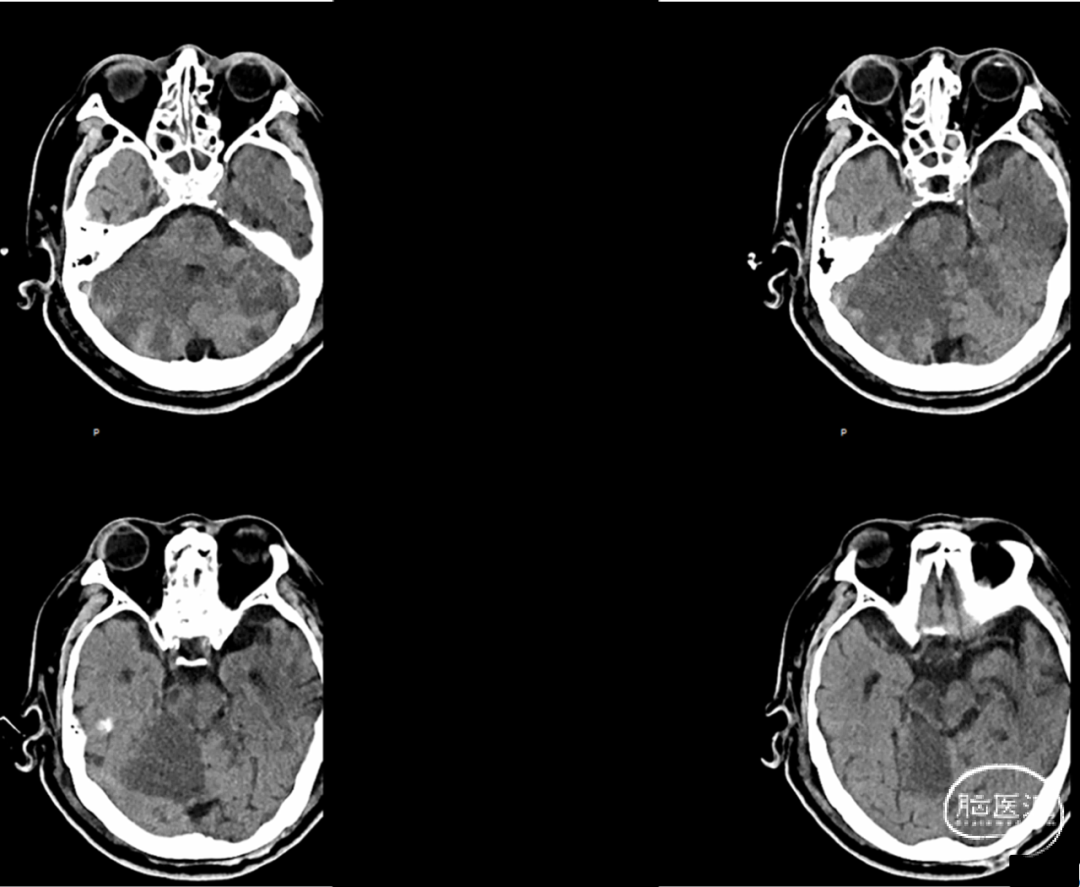

综合术前辅助检查,(Core+pen)/Core=3.58;Pen>15ml;Core<70ml(图3);发病时间小于24小时,存在取栓指征,但是当地医院手术经验告诉我们左侧椎动脉慢性闭塞,且开通异常困难,常规手术方案很难成行,术前制定合理且可行的手术方案至关重要。方案1:仍采用左侧椎动脉+基底动脉取栓的正向开通方案,可能会继续浪费大量时间,甚至最后以失败告终。方案2:采用右侧椎动脉入路,由于右侧椎动脉V4段发育不良,当地医院已尝试过超选,证实无法通过V4段至基底动脉建立取栓通路。方案3:既往有文献报道开颅椎动脉直视下穿刺取栓,虽然方案可行,但我院无类似手术经验,贸然尝试风险难以把控。方案4:回顾当地医院取栓影像资料,发现双侧颈内动脉后交通呈胚胎型,是否可能通过后交通跨循环逆向超选至基底动脉取栓。患者平卧DSA床,全麻插管成功后,用碘伏常规消毒手术区皮肤,铺无菌巾单。取双侧股动脉为穿刺点,于14时00分seldinger法穿刺成功后分别置入8F穿刺鞘和5F 短鞘。行全脑血管造影显示左侧椎动脉起始部闭塞,颈升动脉通过肌支代偿V2及以远的椎动脉血流,右侧椎动脉V4段发育不良,单纯供应右侧PICA,双侧后交通动脉胚胎型。(图9,图10)首先我们仍尝试传统入路进行超选左侧椎动脉,发现左侧椎动脉开口闭塞,斑块质地坚硬,微导丝微导管无法通过。短暂尝试无果后,迅速改为右侧椎动脉入路,发现将微导丝塑型成“J”型或成袢,均无法到达右侧椎动脉V4段,遂果断决定采用跨循环取栓方案。将5F VERT造影导管超选至左侧锁骨下动脉,进行正向血流监测。6F 90cm长鞘(cook)及5F 125cm Navien导管在泥鳅导丝带领下超选进入右侧颈内动脉岩骨段。随后将Rebar18微导管在Synchro2微导丝带领下超选至大脑中动脉,并将Navien带领至右侧颈内动脉交通段。微导丝微导管回撤至颈内动脉,路图下Synchro2微导丝带领Rebar18逐步通过右侧后交通动脉,再在透视下经右侧大脑后动脉P1段盲超选至基底动脉下段。(图11-13)手推造影确认Rebar18微导管已突破血栓段,并在基底动脉真腔内。(图14)经Rebar18释放一枚solitaire FR支架(4mm×20mm)覆盖血栓段。SWIM技术负压下抽拉支架1次,抽拉过程中时刻注意系统张力,逐步回撤支架同时适度回撤Navien释放张力,以保证Navien贴近后交通开口而不向后交通动脉内继续深入。撤出支架后,Navien原位保持负压约30秒。(图15)造影复查见基底动脉及其分支再通,支架取出少量血栓(图18)。于14时45分达到远端血流mTICI3级,10分钟后复查造影显示血管通畅,于14时55分末次造影见远端血流维持mTICI3级。(图16,17)术中Dynamic CT未见明显术区出血(图19)。遂缝合穿刺点,结束手术。手术顺利,术中病人情况稳定。术末血压115/58mmHg,脉搏70次/分,呼吸12次/分,氧饱和度100%。术毕送重症监护室。图9. 双侧椎动脉造影:左侧椎动脉起始部闭塞,左侧颈升动脉肌支和右侧椎动脉通过脊髓支代偿V2及以远的椎动脉血流;右侧椎动脉V4段发育不良,单纯供应右侧PICA

术后予以扩容等中性治疗,控制收缩压≤140mmHg。术后24小时CT见术区未出血(图20),术后24小时CTA+CTP显示基底动脉通畅,后循环灌注恢复(图21,22)。随即加用阿司匹林200mg QD。

图20. 术后24小时CT可见脑组织肿胀,术区未见出血

术后2周患者神志仍昏迷,GCS评分:1T3。气管插管机械通气。双侧瞳孔不等大,左:圆形,直径2.0mm;对光反应消失;右:圆形,直径4mm,对光反应消失,四肢轻度凹陷性水肿。四肢肌张力正常,肌力检查不配合,双侧巴氏征阳性。CT:脑组织水肿消退,脑干小脑多发梗塞灶(图23)。家属要求回当地医院继续康复治疗。